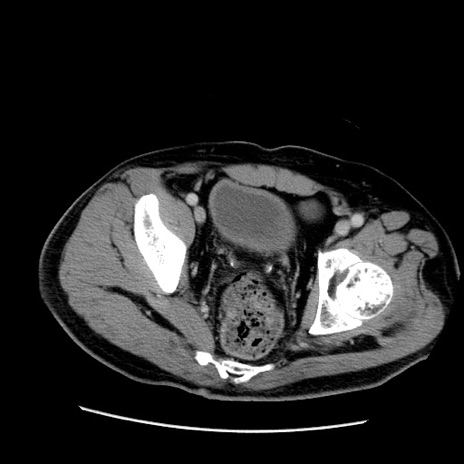

症例22(横断像)

【症例】50歳代男性

【主訴】腹痛

【現病歴】AVMからの被殻出血のため回復期リハ病棟入院中。 本日午後3時頃急に下腹部痛が出現した。

【既往歴】AVM、被殻出血、虫垂炎、高血圧

【身体所見】意識晴明、左半身不全麻痺、会話の理解は良好、36.5°C、腹部:膨隆、全体に板状硬、下腹部正中に圧痛点あり、反跳痛-、筋性防御不明、右下腹部にope scar

【データ】WBC 9400、CRP 0.06